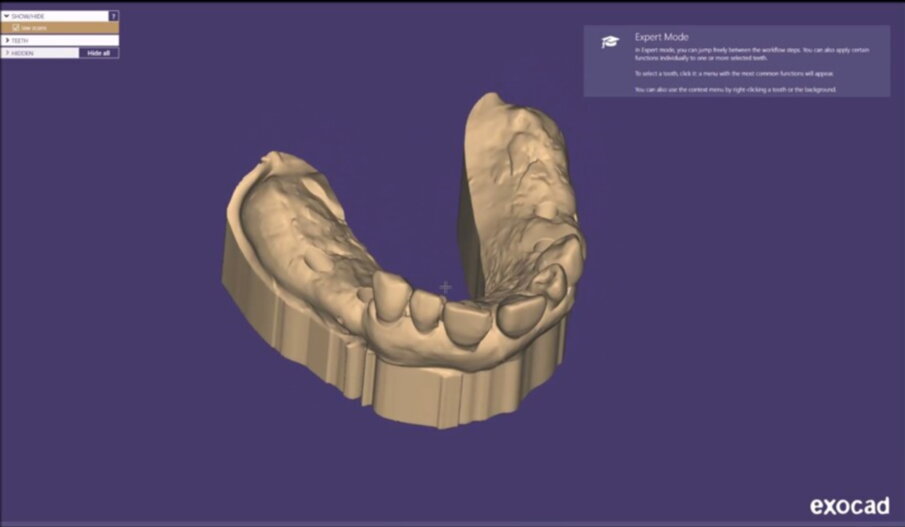

Figg. 13, 14_File STL ottenuti tramite scanner intraorale.

Figg. 21-25_Progettazione Cad con exocad.